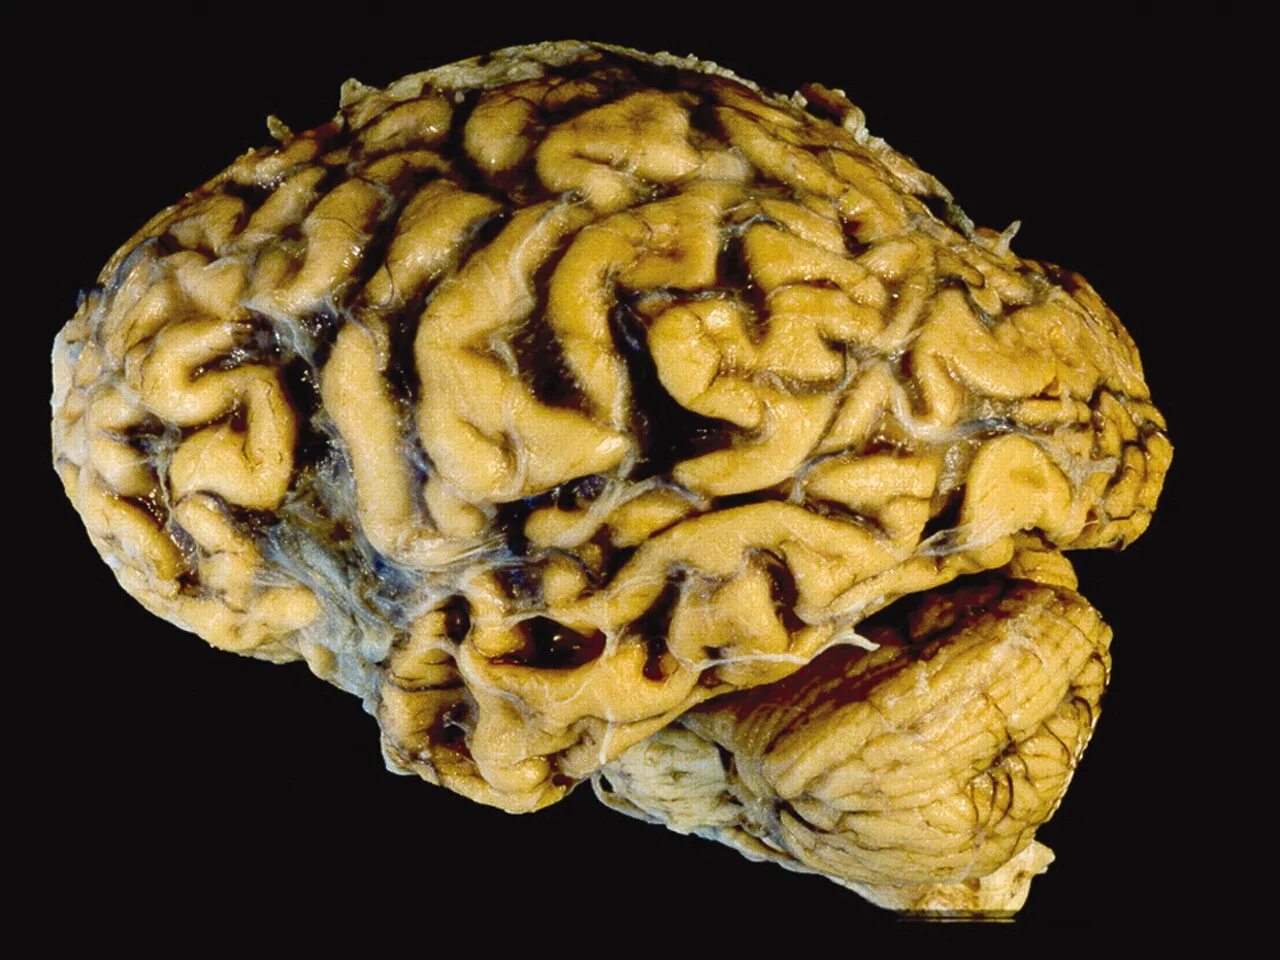

Болезнь головного мозга можно